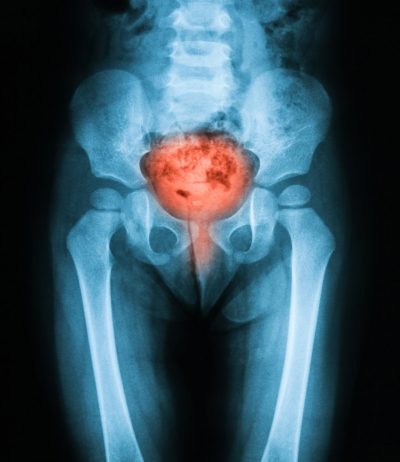

Bladder disorders can significantly impair quality of life and cause distress to patients.

Bladder disorders are often associated with frequent bladder infections, which can lead to renal failure if they are left untreated. Some of the more common types of bladder disorders include: